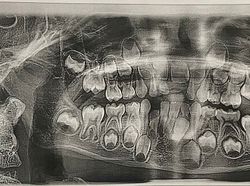

Kondisi Tubuh Manusia Ini Bikin Takjub dan Merinding